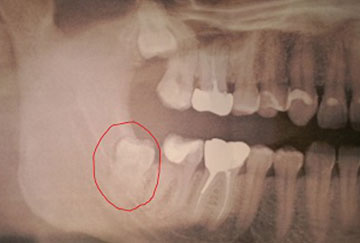

Dent de sagesse